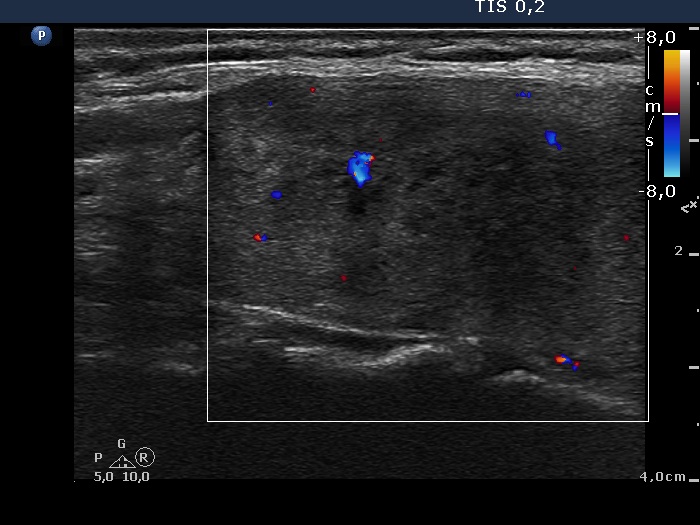

Ultrasonography: there were multiple hypoechogenic areas with ill-defined borders in both lobes, primarily in the right one. The vascularization was decreased.

Ultrasonography: the thyroid decreased in size as did the extent of hypoechogenic areas. The vascularization was unchanged. There was a cystic lesion presenting microcalcification in the solid part in the lower part of the right lobe. We reviewed the video of the first examination and noticed that the lesion was already present but much smaller. The difference in size was explained by the lack at cystic component at first investigation.